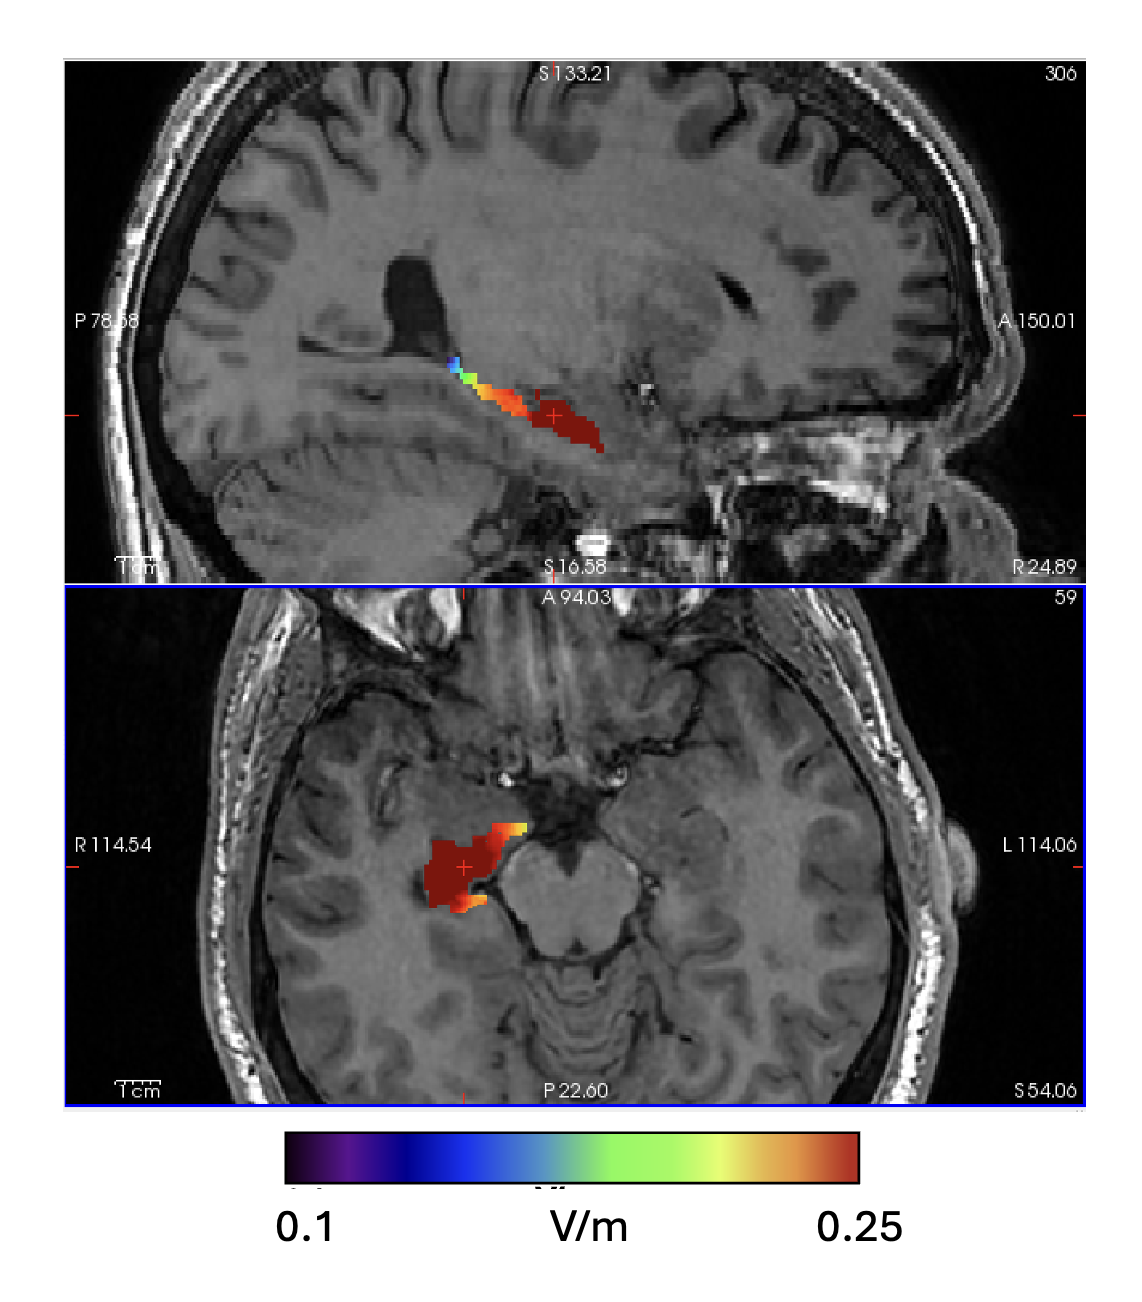

Montage A: TImax field distribution showing intensity map in the sub-cortical ROI (Right Hippocampus).

Montage B: TImax field distribution showing intensity map in the sub-cortical ROI (Right Hippocampus).